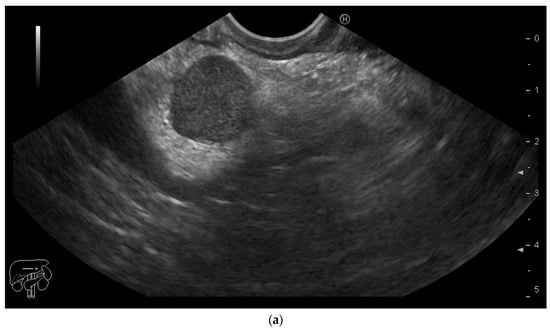

A 54-year-old male ex-smoker was referred by the oncologist for evaluation of a pancreatic mass. Personal medical history was remarkable for left nephrectomy and adrenalectomy 6 months before, for RCC. Follow-up imaging—computed tomography and magnetic resonance imaging—revealed a 16/18 mm pancreatic mass suggestive of a neuroendocrine tumor. He had no digestive complaints. Physical examination was unremarkable, except for a post-operative left flank scar. Laboratory work-up showed mild normocytic anemia. Tumor markers (CEA, CA 19-9, CA 125), serum chromogranin, serotonin and urinary 5-hydroxyindoleacetic acid were within normal limits. We performed endoscopic ultrasound (EUS) to further characterize the pancreatic mass and obtain a histopathologic diagnosis. EUS showed a well-delineated, round hypoechoic lesion in the pancreatic isthmus (Figure 1a), with a hard homogeneous pattern on elastography (Figure 1b). Upon administration of contrast media (SonoVue), rapid uptake of contrast was seen in the arterial phase, with washout in the late phase (Figure 1c,d). A fine-needle biopsy (FNB) was performed using a 20 G ProCore needle, and the histopathology report confirmed the diagnosis of metastatic RCC in the pancreas (Figure 1e,f). Following the oncology board’s decision, the patient was referred for surgery. No recurrence of metastatic lesions was found on imaging at the one-year follow-up.

(a) Endoscopic ultrasound using a linear probe: hypoechoic mass in the isthmus of the pancreas. (b) Real-time elastography showing a hard homogeneous pattern in the lesion. (c) Contrast-enhanced EUS showing a hyperenhancing pattern of the lesion in the arterial phase. (d) Contrast-enhanced EUS image showing washout of the lesion in the late phase. (e,f)—Hematoxylin-eosin stain, 100× and 200× magnitude, showing RCC tumor proliferation.